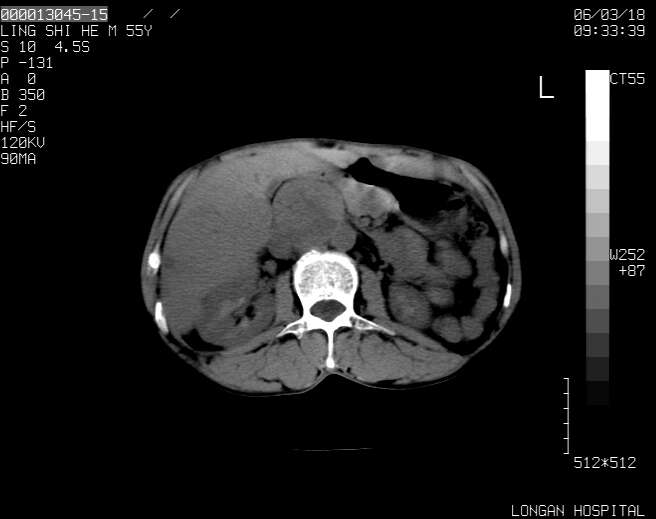

以下是引用guzhongliangddd在2006-3-21 22:13:00的发言:[br]病灶主要位于肝右叶的后份,内见异常血管,门脉主干及右支受侵{提示有癌栓形成},门腔间隙内见增大淋巴结。肝左叶内未见异常。

以下是引用zhuxinli在2006-3-22 1:23:00的发言:[br][br] 病灶主要位于肝右叶的后份,内见异常血管 .门脉右支截断,右叶前段早期强化(考虑动静脉漏),腹膜后肿大淋巴结,病灶逐渐强化,考虑为胆管细胞癌[br]